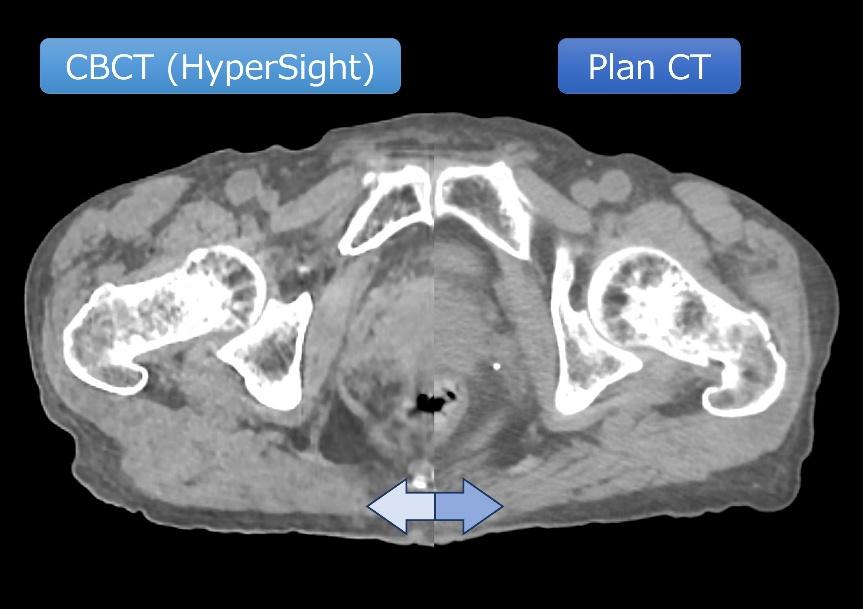

高精細CBCT(HyperSight)

HyperSight は、高画質かつ高速撮影に対応した画期的なCBCT(コーンビームCT)機能です。治療直前に患者さんの体内位置を三次元的に確認し、照射位置の再現性向上を図ります。

検出器の改良により、従来のCBCTと比較して撮影時間が短縮されるとともに、画質も大きく向上しました。これにより、高精度な位置合わせを短時間で行うことが可能です。

また、CT値(CT画像の各画素が持つ信号値)の精度が向上したことで、CBCT画像を利用した再治療計画が可能となりました。腫瘍の大きさや体内臓器の変化に応じて治療計画を適宜見直す治療法は、適応放射線治療(Adaptive Radiotherapy:ART)と呼ばれます。